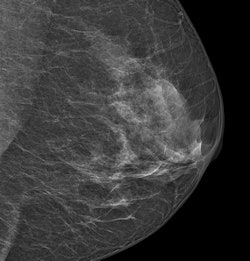

An image acquired with Philips' MicroDose SI system. Image courtesy of Philips.

MicroDose SI uses digital photon-counting technology, which allows clinicians to conduct exams using low radiation dose without compromising image quality; the company received 510(k) clearance from the FDA for the device in February.

High breast density is a known risk factor for breast cancer, and interpretation of mammograms of dense breast tissue is more difficult. Philips' breast density software is the first application the company has developed to interpret the spectral data obtained from MicroDose SI by giving radiologists a density score that works with BI-RADS classifications, according to the company.